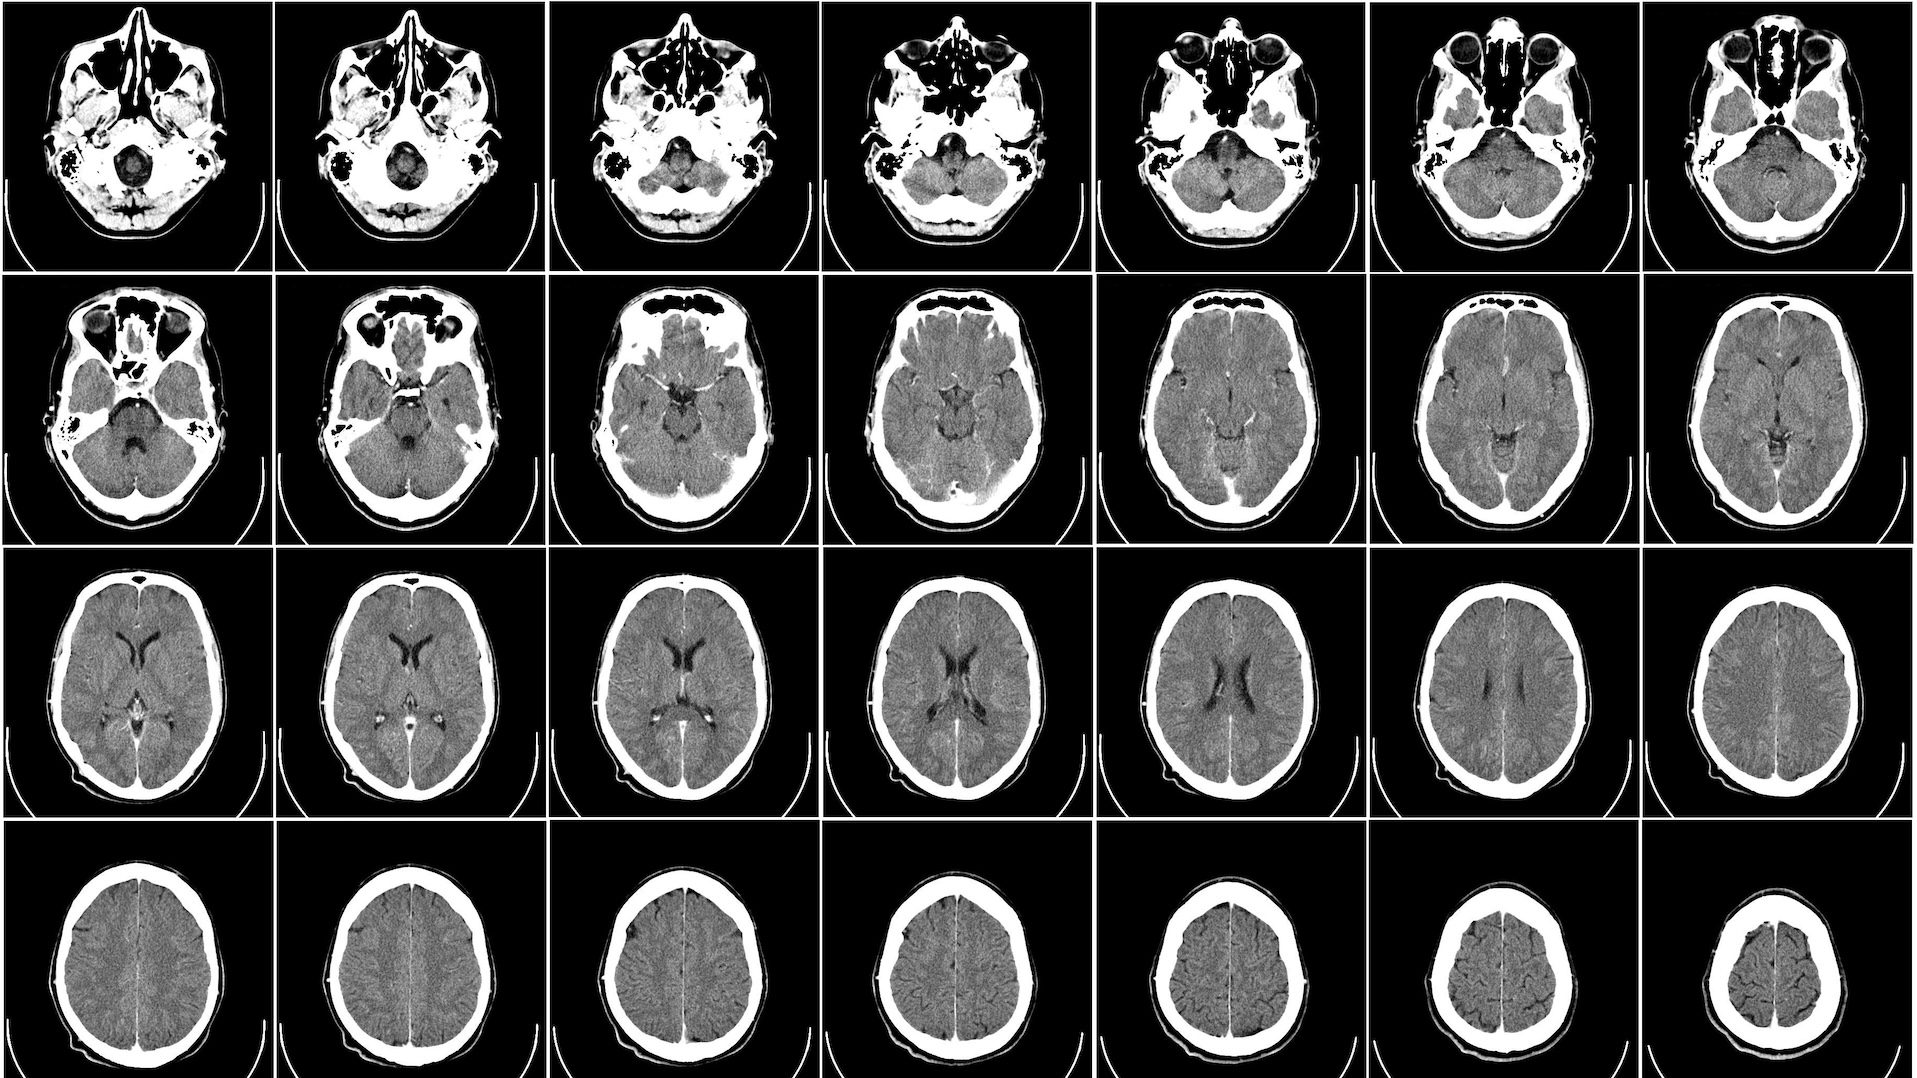

Например, шизофрения и биполярное расстройство. Симптоматика разная, но есть много генов, характерных для обоих этих заболеваний: около 70% генетических факторов риска шизофрении оказалось характерно и для биполярного расстройства. Или СДВГ (синдром дефицита внимания и гиперактивности) и аутизм, которые в психиатрических справочниках классифицируются даже не как разные заболевания, а как целый спектр из множества заболеваний, но с точки зрения генетики все они имеют общую базу, во всяком случае — общие генетические корреляты. Важно, что некоторые из этих генов активны уже в формирующемся мозге эмбриона, задавая базовые особенности его нейроархитектуры.

- шизофрения и биполярное расстройство — оказалось, важную роль в возникновении этих расстройств играют нарушения в работе возбуждающих нейронов и формируемых ими синапсах в коре и гиппокампе;